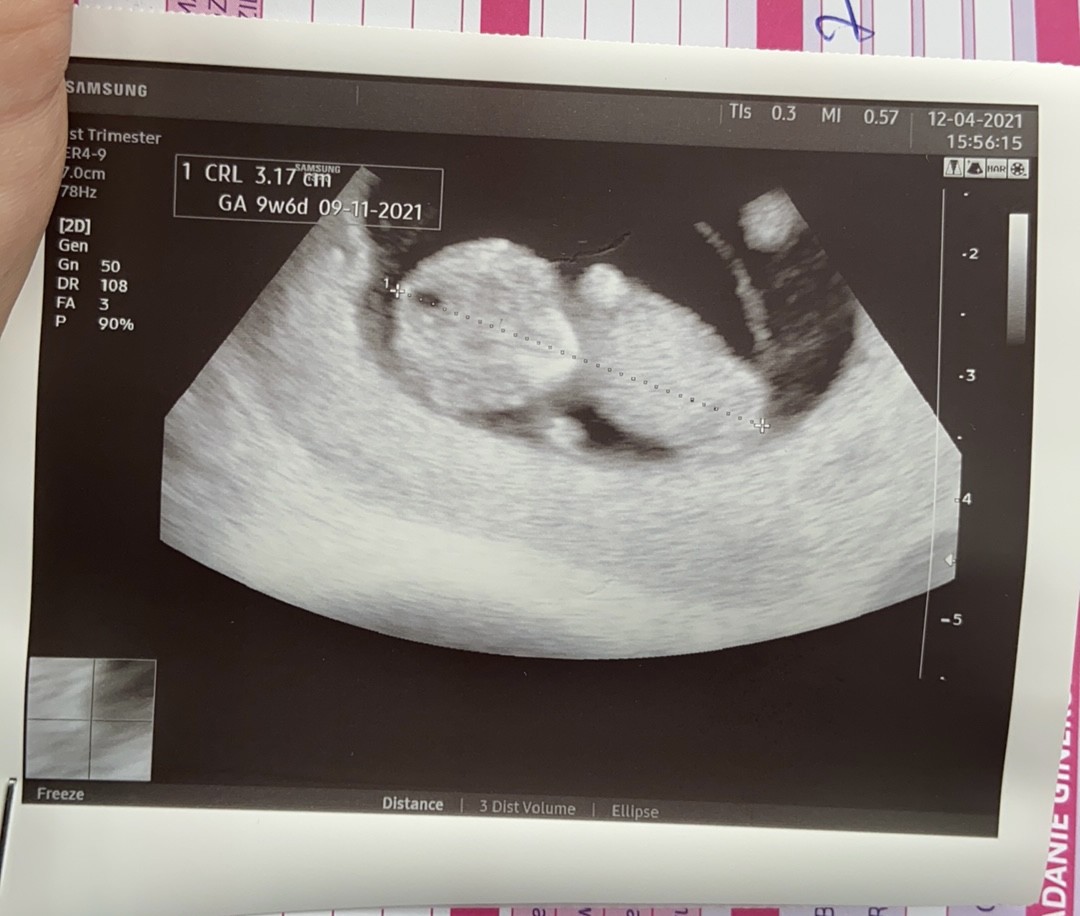

Odnośnie hemoglobiny i hematokrytu to nie jeść źle, też mam obniżone ponieważ to normalne w pierwszym etapie ciąży ze względu na zwiększoną objetosc krwi.